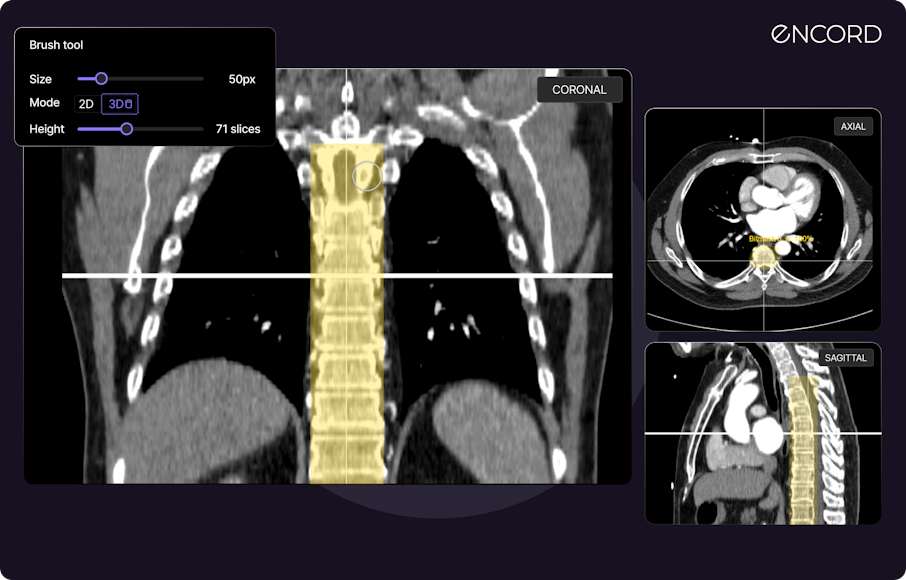

Our latest updates to MPR allow you to create Bitmask annotations directly on reconstructed views, and in any annotation window within the Label Editor. Annotations made in the one view automatically appear in all other views, and cross-reference lines are projected across all three views, assisting with precise anatomy annotation.

All reconstructed views can also be transformed into detailed 3D renderings that prominently display your annotations.

Step 1: Open a DICOM annotation task in the Label Editor. The primary view is your main workspace, positioned on the left in the Label Editor. Reconstructed views are conveniently placed on the right.

Step 2: Select a Bitmask object, and apply a label on any window. Use the 'Annotate from this tile' button to change the tile you're working on.